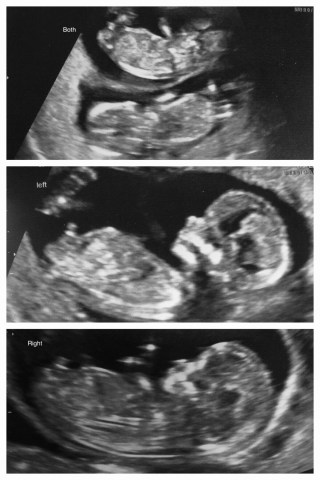

Lots of ‘good on you’s and lots of ‘you’re very brave’ (I’m not sure if that’s directed at the on my own, or the twin thing!) I’m not sure if I am brave, or stupid, I guess I’ll find out in September!